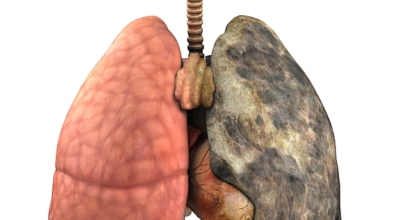

폐암은 폐에 생긴 악성 종양입니다. 폐 자체에 나타나는 원발성 폐암과 다른 장기에서 전이되어 온 전이성 폐암이 있습니다. 전 세계적으로 해마다 130만 명이나 되는 사람들이 폐암으로 사망하는데 이는 암에 의하여 사망하는 것 중에 가장 높은 비중을 차지하고 있습니다.